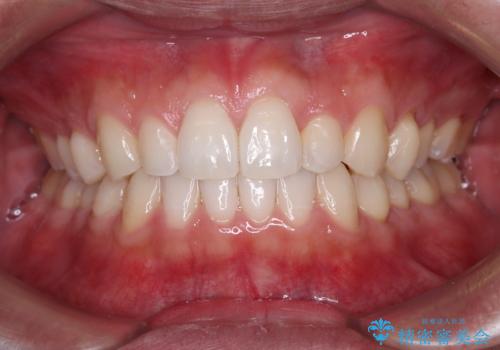

[ 前歯のねじれ・がたつき ] マウスピース矯正

![[ 前歯のねじれ・がたつき ] マウスピース矯正の症例 治療前](https://seimitsushinbi.jp/wp/wp-content/uploads/2024/02/4007c6479f6bce11863dcdd32ed5e39b-500x350.jpg?v=1708502552)

![[ 前歯のねじれ・がたつき ] マウスピース矯正の症例 治療後](https://seimitsushinbi.jp/wp/wp-content/uploads/2024/02/e7a01485e4f4dd0da04705fde4cc34cc-500x350.jpg?v=1708502585)

インビザライン モニター治療 前歯のねじれをまっすぐに